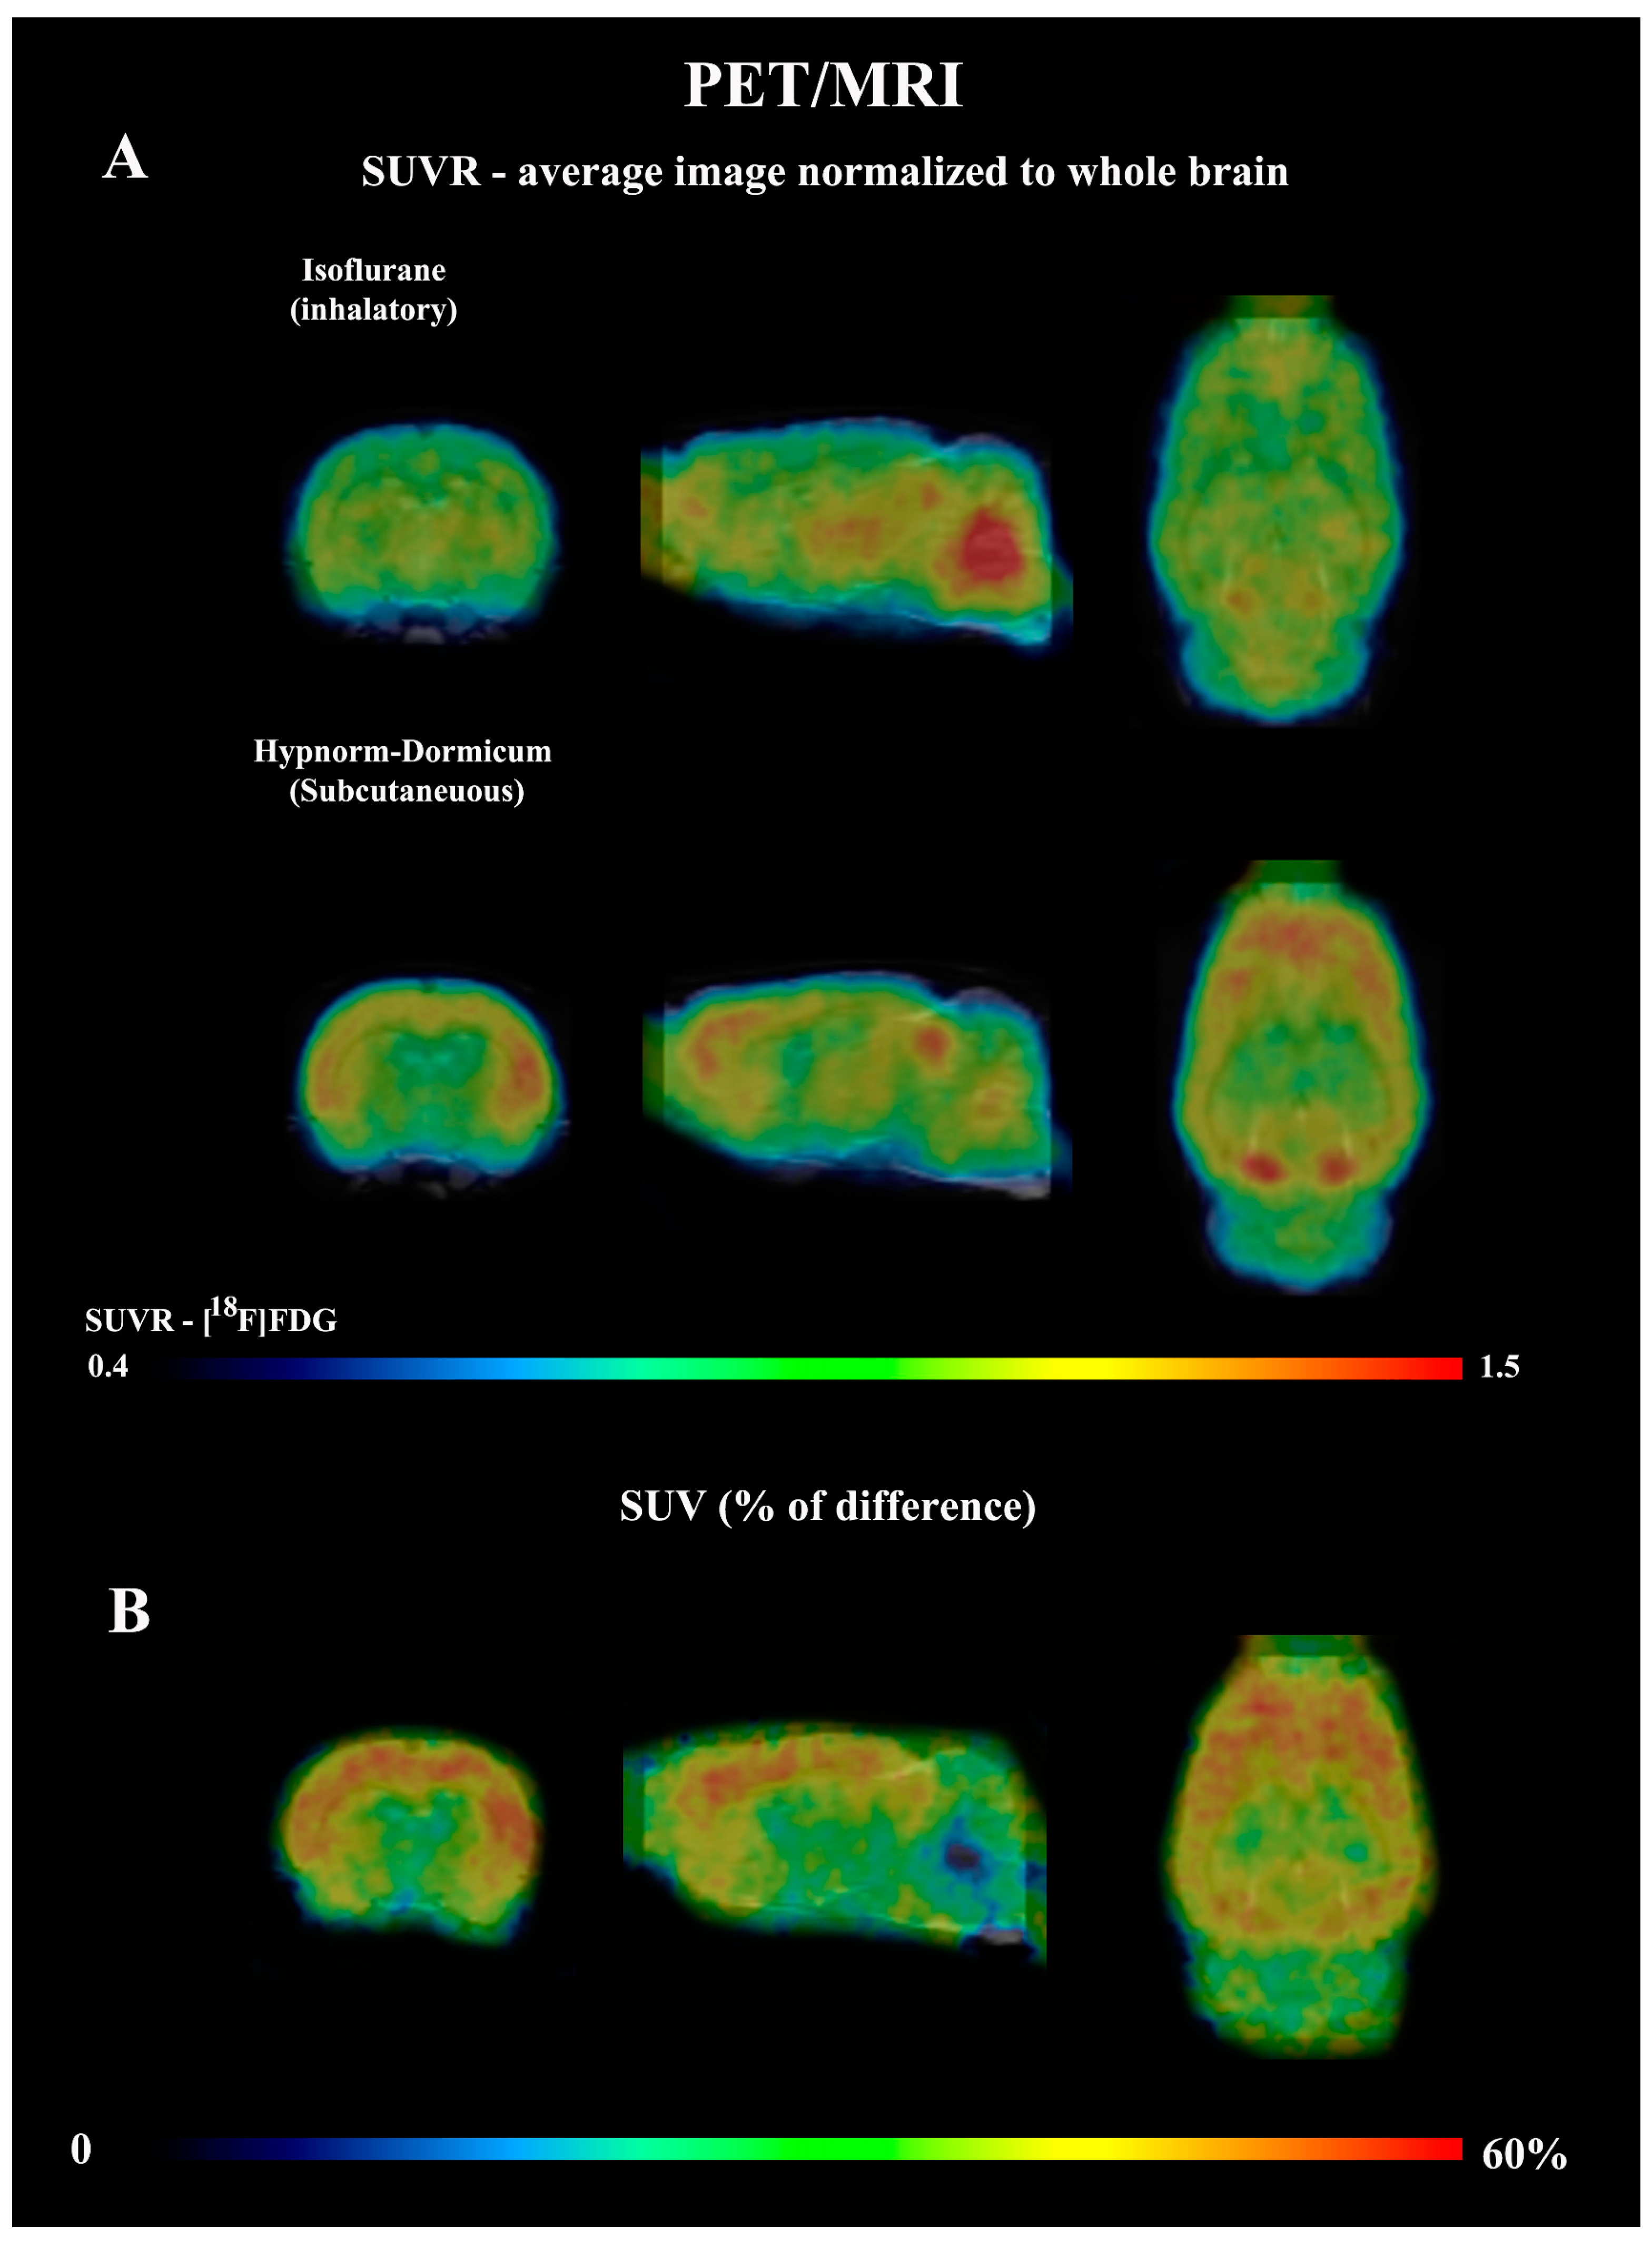

3.3. [18F]FDG PET Imaging—Voxel-Based Analysis—Brain

| Cluster Level | Voxel Level | Coordinates | Brain Area | |||||

|---|---|---|---|---|---|---|---|---|

| PFWE-Corr | kE | T | Puncorr | x | y | z | ||

| Isoflurane < Hypnorm–Dormicum | <0.0001 | 20,055 | 12.15 | <0.0001 | 5.4 | 0.8 | −4.2 | Right Primary somatosensorial cortex |

| 9.6 | <0.0001 | −3.4 | 2.4 | −1.6 | Left Primary motor cortex | |||

| 5.49 | <0.0001 | 3.4 | −6.6 | −1 | Right Primary motor cortex | |||

| <0.0001 | 1207 | 8.25 | <0.0001 | −3 | −6 | −1 | Left visual cortex | |

| 0.025 | 465 | 6.08 | <0.0001 | 7 | −3 | −3.6 | Right Primary motosensorial cortex | |

| Isoflurane > Hypnorm–Dormicum | <0.0001 | 6480 | 7.44 | <0.0001 | 0.2 | −5.6 | −5.8 | Dorsomedial periaqueductal gray |

| 0.088 | 313 | 5.86 | <0.0001 | −0.4 | −11.8 | −2 | Left molecular layer cerebellum | |